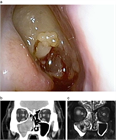

1. 原疾患の病態(感染やアレルギーなど)に応じた治療を行う。鼻粘膜腫脹に対する対症療法としては、鼻処置などによる血管拡張と粘膜下浮腫の除去を行う。